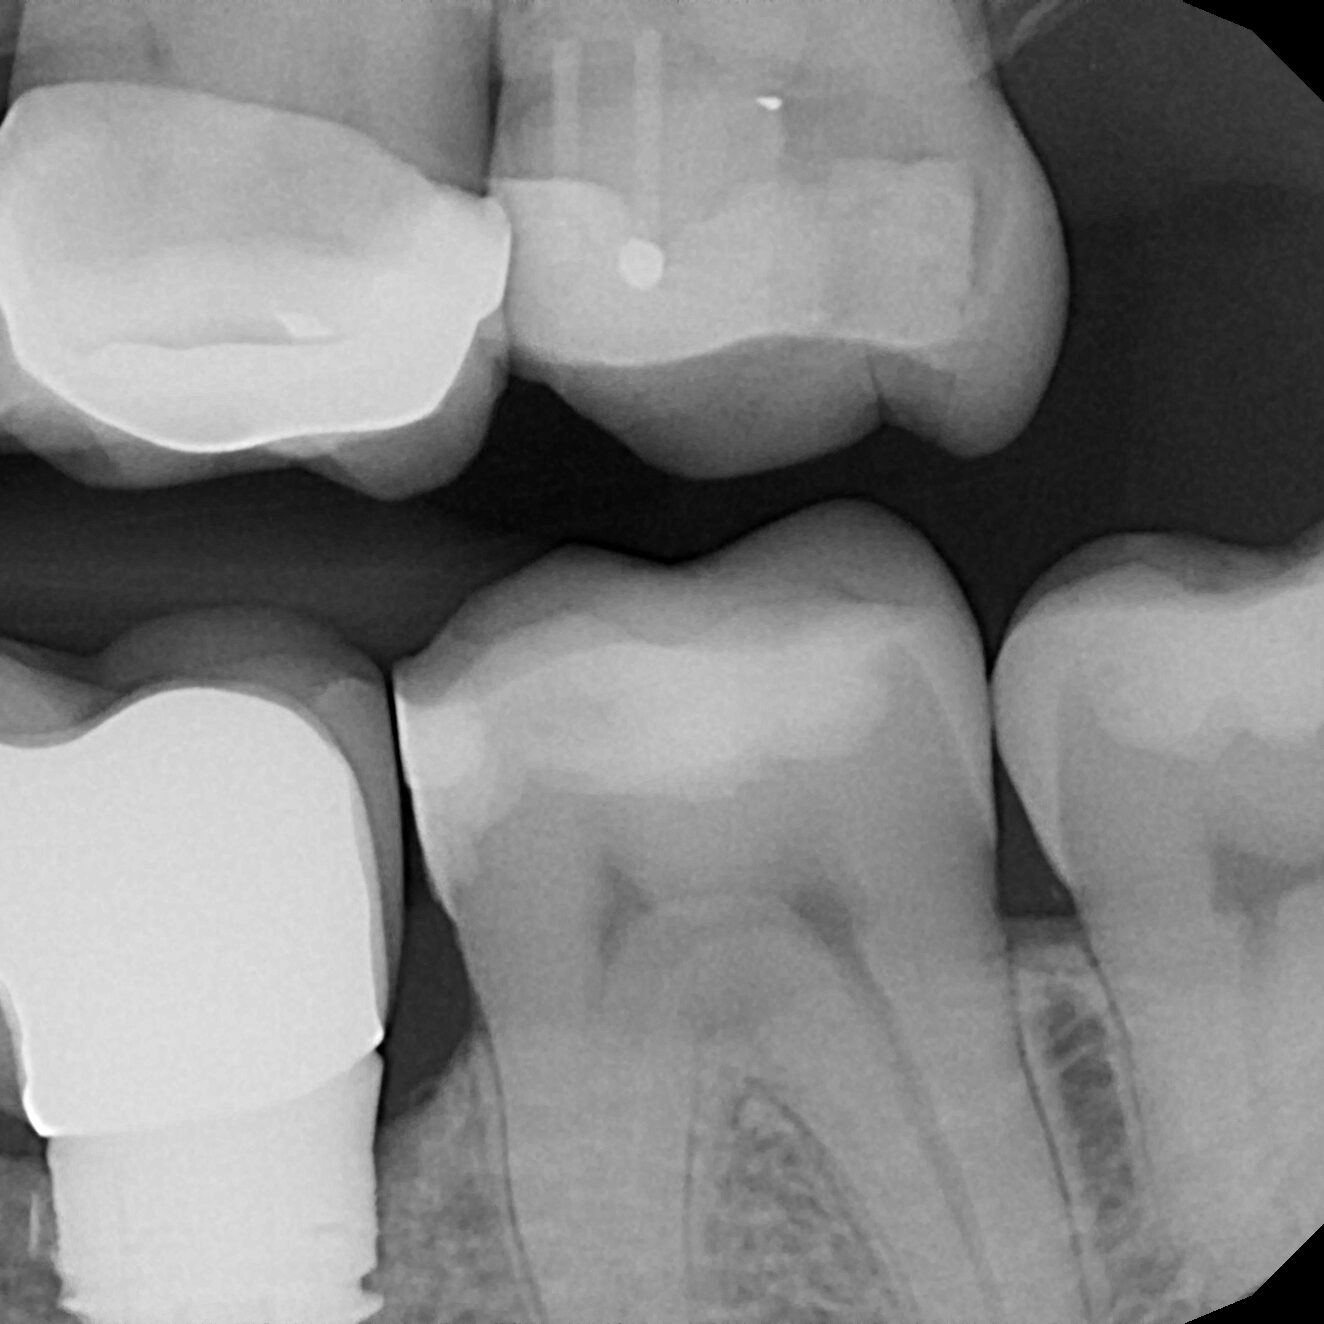

Chip

Chipped Tooth – how many of these do you see and repair without long-term success?